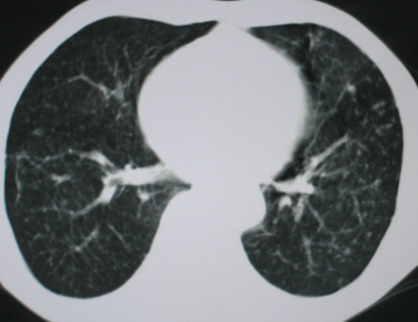

以下是引用医影拾贝在2008-6-3 18:48:00的发言:[br]双上肺弥漫性小结节影,纵隔窗内钙化淋巴结影,考虑血播性tb可能性较大,不除外肺ca可能

以下是引用卜一在2008-6-3 19:33:00的发言:[br]双肺结节,以双上肺分布为多,期间搀杂片状致密影及索条致密影。考虑:继发性肺结核伴血型播散可能性大。不除外肺泡ca的可能!另:椎体退变!

以下是引用panyishengct在2008-6-3 21:09:00的发言:[br]双上肺弥漫性小结节影,纵隔窗内钙化淋巴结影,考虑矽肺或/和tb可能性较大,不除外肺ca可能。腰椎考虑退变。 [br][br]